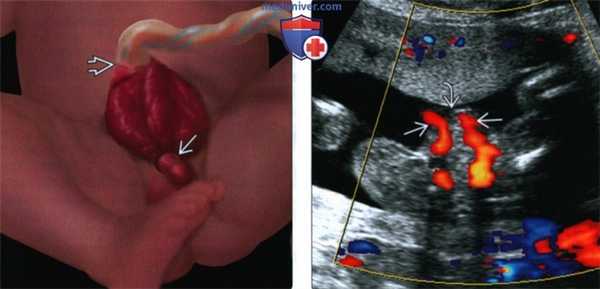

(Слева) 3D УЗИ с поверхностной реконструкцией. Между ног плода определяется дефект передней брюшной стенки, сопровождающийся выпадением петель кишечника между половинами экстрофированного мочевого пузыря (признак «хобота»).

(Справа) Клоакальная экстрофия. Изображено омфалоцеле, при этом терминальный отдел подвздошной кишки выпадает между двумя половинами экстрофированного мочевого пузыря. Картина выпадающей толстой кишки получила название признака «хобота». Следует помнить, что омфалоцеле не относится к обязательным критериям диагностики данного порока.